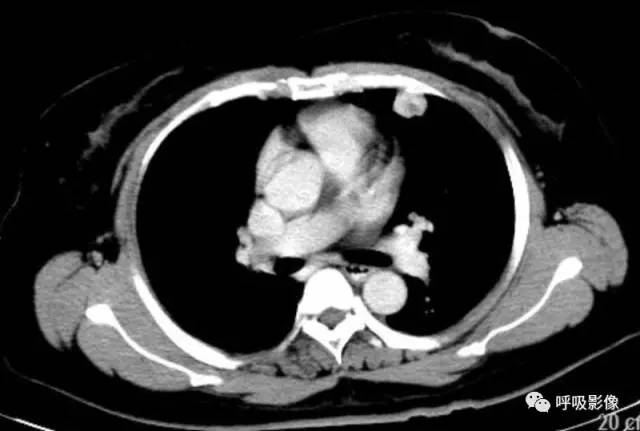

绒毛膜癌较侵袭性葡萄胎易发生转移。侵袭性葡萄胎肺部转移多以结节为主(图1),而绒毛膜癌肺部转移种类较多。

图1 女,31岁,侵袭性葡萄胎